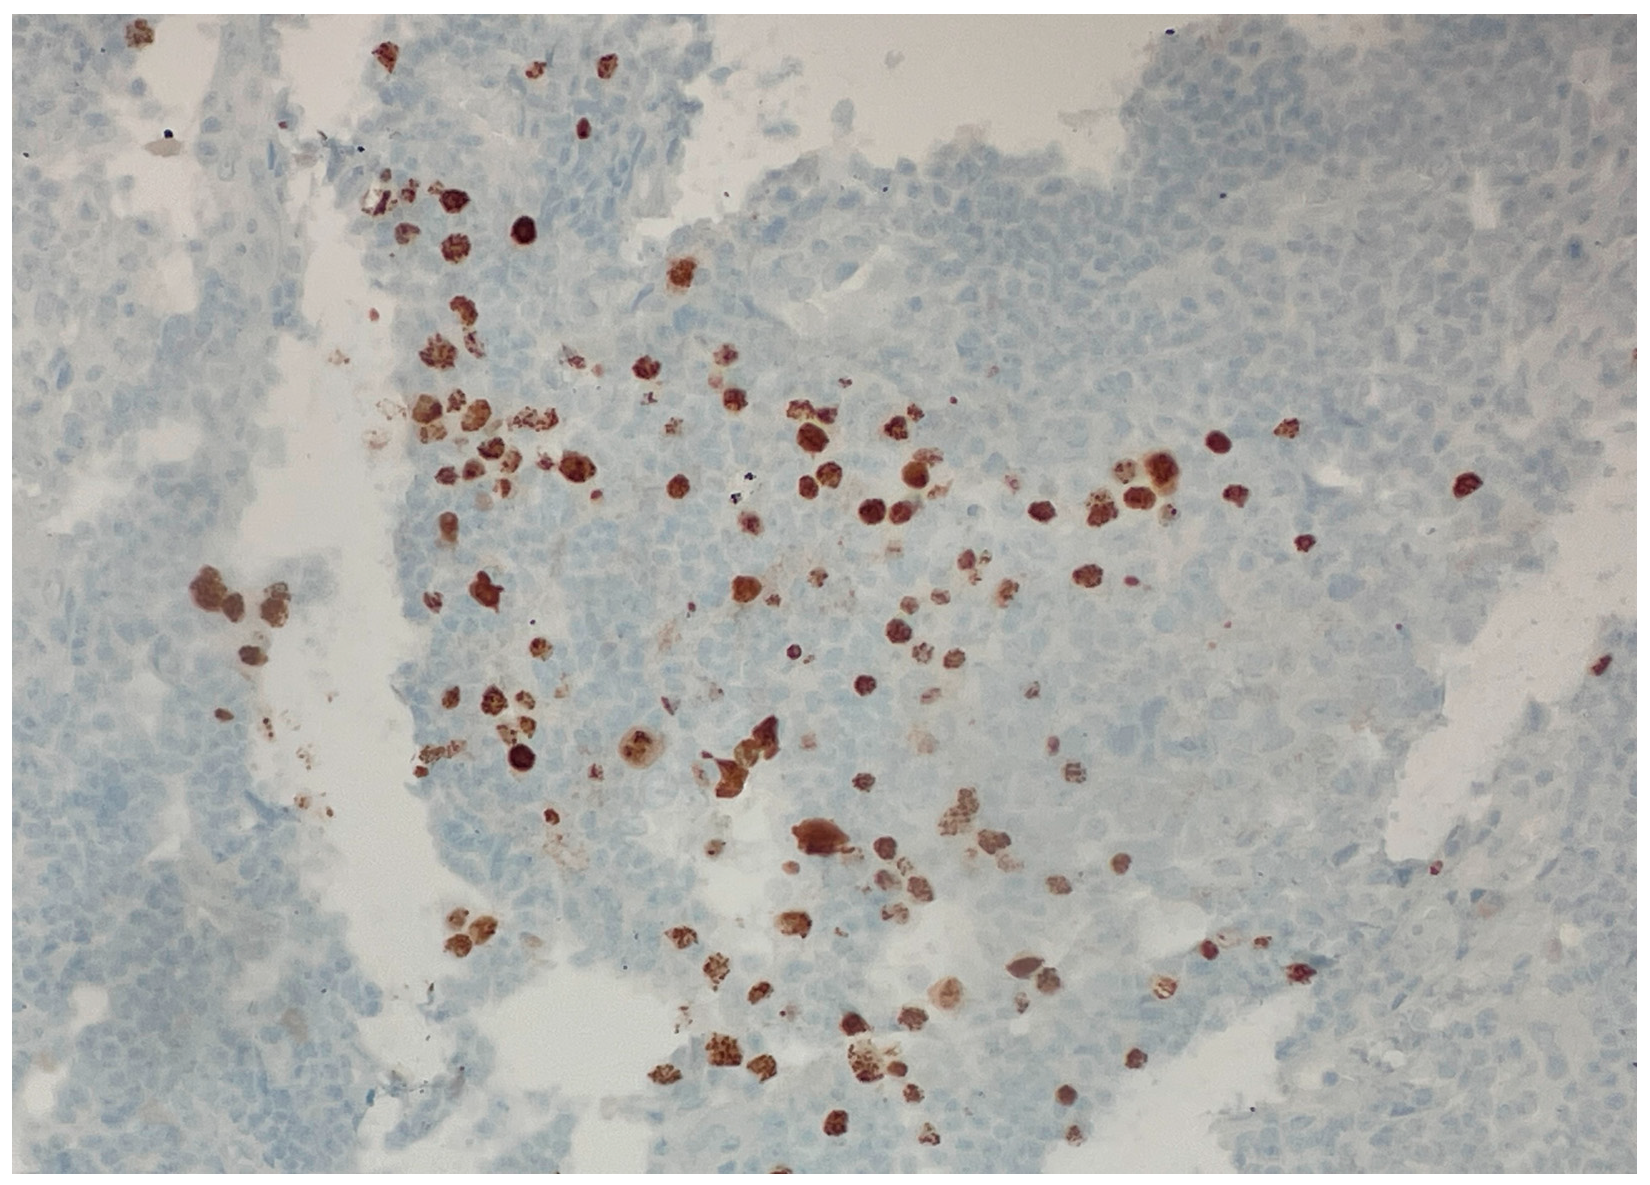

Over the following weeks, the patient developed ascites and worsening constitutional symptoms. An excisional biopsy of a lymph node was subsequently performed and demonstrated HHV-8-positive MCD, confirmed by immunohistochemical staining for LANA-1, showing scattered nuclear positivity in lymphoid cells (Figure 1). The histology also revealed characteristic “onion skinning” of mantle zone lymphocytes (Figure 2) and regressed germinal centers with increased interfollicular vascularity and hyalinization (Figure 3), findings consistent with HHV-8-associated MCD. Rituximab monotherapy was initiated, resulting in clinical improvement, resolution of the constitutional symptoms, and stabilization of ascites.

Figure 2. Higher-power view of secondary follicle showing characteristic “onion skinning” of mantle zone lymphocytes. (H&E, 20×). This histopathologic feature can be seen in all types of Castleman disease. The concentric layering of small lymphocytes around atrophic germinal centers resembles an “onion skin” pattern.

Figure 3. Low-power view of secondary follicles showing regressed germinal center and prominent interfollicular vascularity. (H&E, 10×). The follicle on the bottom shows an atrophic and partially hyalinized germinal center. The follicle on the top shows a vessel penetrating the germinal center (“lollipop” feature). These features can be seen in all types of Castleman disease.

The distinction between a core needle and excisional biopsy is critical because delays in performing excisional biopsies frequently prolong the diagnostic timeline, consequently delaying the initiation of essential treatment. In accordance with published consensus criteria, the excisional biopsy for our patient not only confirmed the diagnosis, but also revealed classic MCD histopathologic features, including the characteristic “onion skinning” mantle zones and the presence of LANA-1-positive plasmablasts [1].